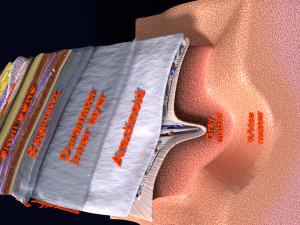

Brain with meninges scalp detailed labelled 3D 3D मॉडल

A blend model of brain along with its covering layers (meninges), skull bone and scalp labelled in detail and anatomically precise. The parts depicted are white, gray, pia, arachnoid, dura, bone, skin, fat, aponeurosis, periosteum, falx cerebri and more.

The material is high resolution image textures and normal maps based on non overlapping UVs. The texture and normal maps are packed with the blend file itself.